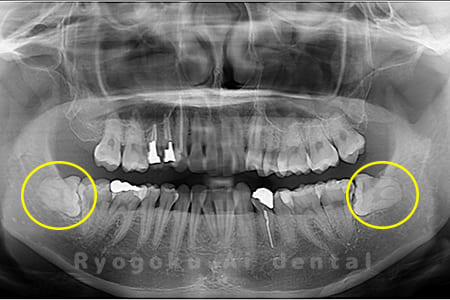

Case01

- 原因

- 水平埋伏智歯

- 治療内容

- 下顎の水平埋伏智歯を抜歯

<リスク・副作用>

手術後は痛み、腫れ、痺れなどの副作用が生じる場合があります。